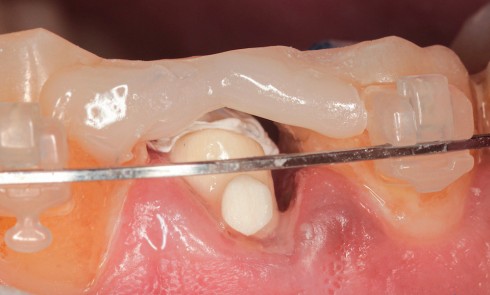

Article réservé à nos abonnés Extraction, implantation et temporisation immédiate : recycler la dent naturelle ? À propos d’un cas clinique

Les protocoles d’extraction-implantation immédiate, décrits pour la première fois en 1976 par Schulte et Heimke [1], se sont progressivement développés...